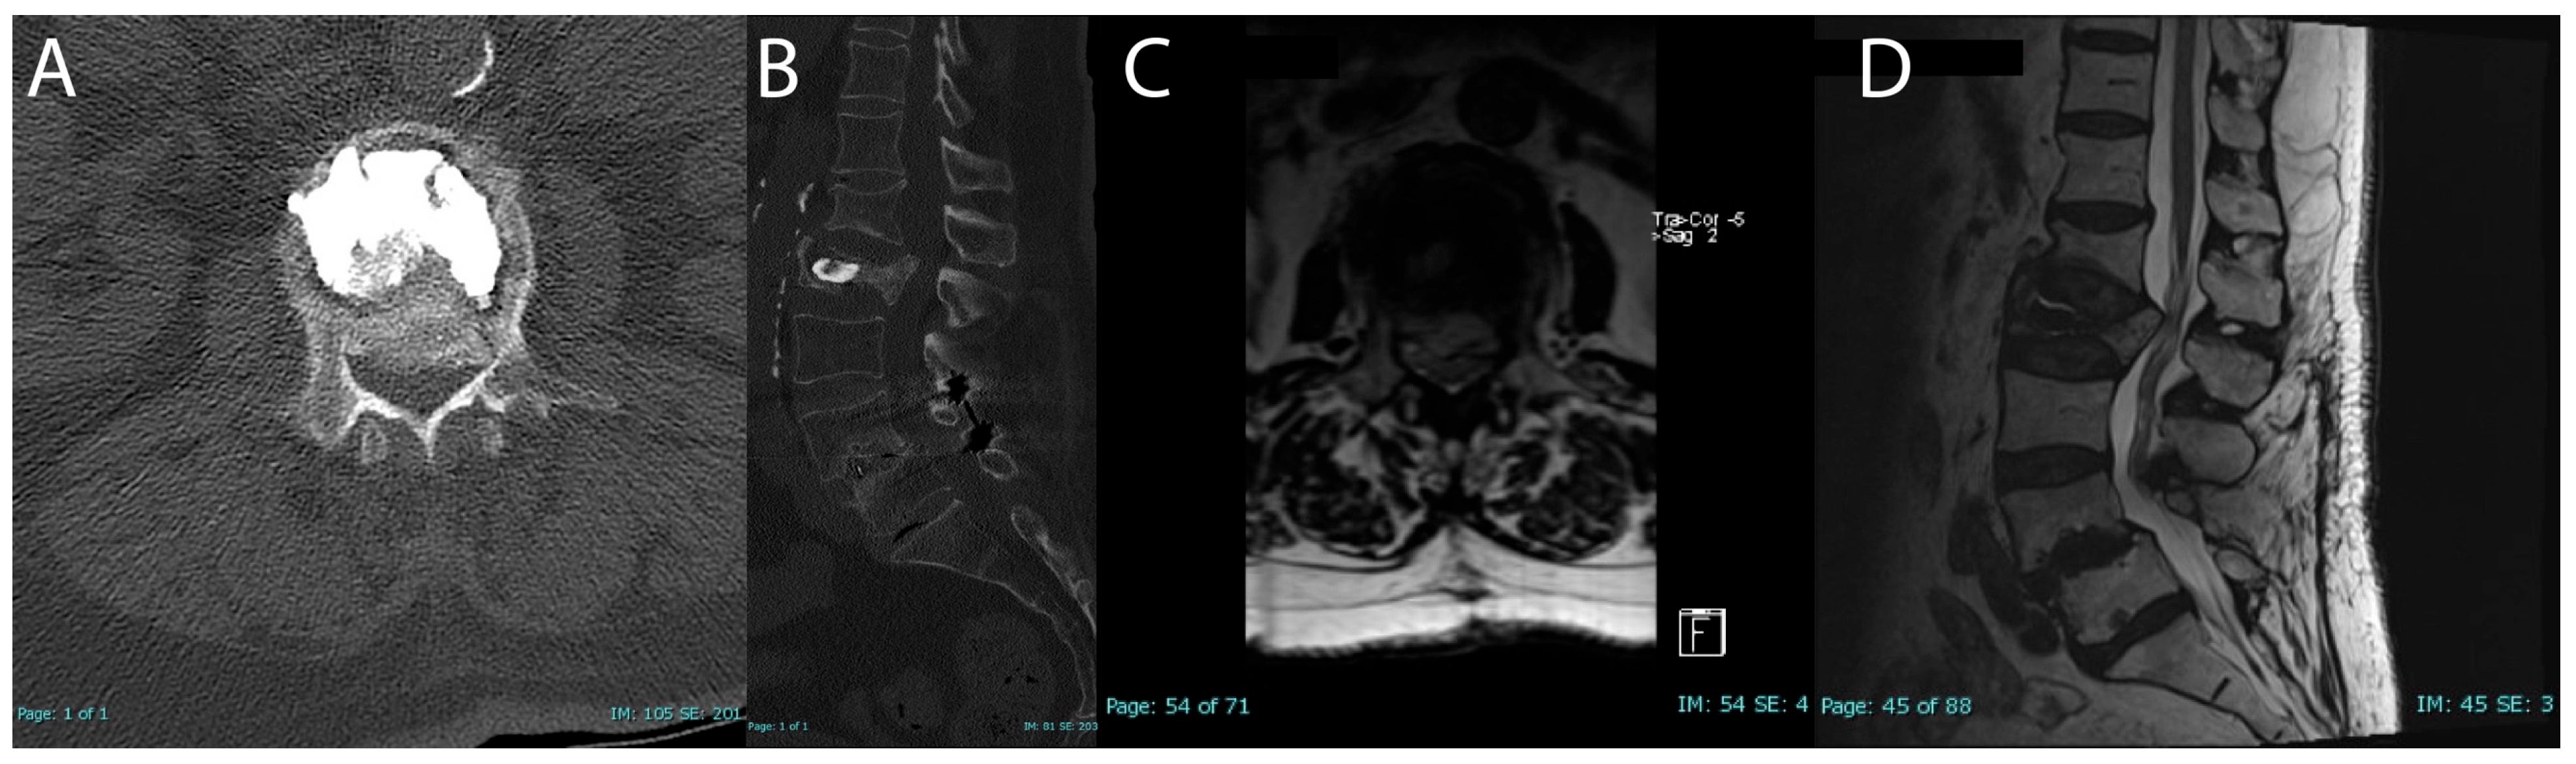

On follow-up upright standing X-rays, only one patient had a potentially unstable finding of possible settling of fracture around cement. One-month follow-up MRI showed significant settling of the L2 burst fracture with retropulsion into the canal with significant central lateral recess stenosis (Figure 4). The patient had no significant mobility issues. The pain was tolerable but was not improving. The patient was offered spinal surgery as well as conservative management for the pain. The patient chose to manage with injections and physical therapy and at three-month follow-up, the patient’s pain and mobility had improved.

Importantly, only one complication was recorded. Case 2 presented to their follow-up appointment at one month postoperative with severe left hip and thigh pain, which was later attributed to a progressive settling of the fracture and retropulsion of bony fragments into the spinal canal. CT and MRI findings confirmed that there was moderate to severe canal stenosis at L1–L2 with worsening retropulsion (Figure 3). Despite these findings, the patient’s mobility remained stable but pain was causing significant distress. After being offered both surgical and conservative options, the patient chose conservative management with physical therapy and epidural steroid injections, which led to a gradual improvement in pain and functionality over the next two months. After two sessions, the patient no longer required assistance with ambulation and was pleased with the improvement in pain, withdrawing from any further evaluation. Chart review revealed the patient did not have any further injections or spinal surgery after her last follow-up appointment.

Figure 4. Follow-up complication for case 2 (AD); one-month postoperative CT axial (A); CT sagittal (B); one-month postoperative MRI axial T2 (C); MRI sagittal T2 (D).